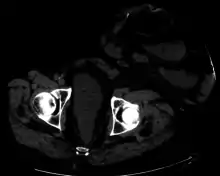

![]() Diagram showing a colostomy | |

A colostomy is an opening (stoma) in the large intestine (colon), or the surgical procedure that creates one. The opening is formed by drawing the healthy end of the colon through an incision in the anterior abdominal wall and suturing it into place. This opening, often in conjunction with an attached ostomy system, provides an alternative channel for feces to leave the body. Thus if the natural anus is unavailable for that function (for example, in cases where it has been removed in the fight against colorectal cancer or ulcerative colitis), an artificial anus takes over. It may be reversible or irreversible, depending on the circumstances.

Placement of the stoma on the abdomen can occur at any location along the colon, but the most common placement is on the lower left side near the sigmoid where a majority of colon cancers occur. Other locations include the ascending, transverse, and descending sections of the colon.[4]